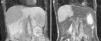

HHs are suspected when ultrasonography shows nodules with homogeneous hyperechogenicity, but additional imaging tests, usually triphasic computed tomography (TCT) or magnetic resonance imaging (MRI), are required to confirm the diagnosis due to the lack of specificity of ultrasonographic findings. TCT typically reveals progressive enhancement during the arterial phase in a centripetal fashion. MRI shows a low signal intensity on T1-weighted images, high signal intensity on T2-weighted sequences, and an inward enhancement after gadolinium administration can be seen.14 Tc-99m-labeled red blood cell single emission photon computed tomography may be helpful when there is diagnostic uncertainty; it has sensitivity, specificity and accuracy of 97%, 83%, and 96%, respectively.15 Positron emission tomography is useful to differentiate heterogeneous HH from angiosarcomas.16 The differential diagnosis includes angiomatosis, metastases, hematic cyst, hepatic peliosis, and hepatocellular carcinoma, among others.

MethodsWe performed a retrospective analysis of patients with HH at our hospital within the time frame of January 1, 1990 and November 31, 2008. We made an electronic search regarding outpatient and inpatient hospital records looking for the diagnosis of hemangioma and/or benign hepatic tumor, which corresponded to the D 18.0 and D 13.4 categories of the CIE 10, respectively. We included all patients with GHH and HH, and diagnosis was based on the presence of conclusive imaging findings on TCT or MRI (peripheral nodular enhancement in the early phase followed by centripetal enhancement during the late phase) (figs. 1-4) or on the histopathology report. Medical records were reviewed for each patient to obtain demographic, clinical, radiological, and laboratory information, evolution, and treatment; if surgery was performed, data regarding the type of surgery, duration, complications, and transfusion requirements were recorded. Pain due to HH was defined as persistent pain in the upper right abdomen that could not be better explained by an alternative diagnosis, including irritable bowel syndrome.

Triphasic Computed TomographyA 16 or a 64-slice multidetector CT (Somatom, Sensation 16 or 64; Siemens Munich, Germany) was used; images were obtained with a section thickness of 3-5mm and a reconstruction interval of 2-2.5mm. All cases were analyzed on a workstation with the capacity to produce coronal reformatted images. All patients received both intravenous and oral contrast. For intravenous contrast, 120ml of Conray (Mallinckrodt Baker Inc., St Louis Missouri, USA) was given 45 s prior to performing the scan; for oral contrast, 40ml of Ioditrast M60 (Justesa Imagen Mexicana) were diluted in 1,000ml of water and given to all patients orally one hour prior to computed tomography. All TCT images were analyzed by at least 2 certified radiologists.

Magnetic resonance imagingMagnetic resonance imaging (MRI) was performed on a 1.5 T system (Signa Excite HD, GE Healthcare, Milwaukee, USA), using a variety of software upgrades that evolved during the study period. Standard liver imaging sequences included T1-weighted In-phase and Opposed-phase gradient echo and T2-weighted fast spin echo sequences. T1-weighted imaging was repeated after contrast material administration during hepatic arterial (19-25 s), portal (40-45 s), venous (60-65 s) and delayed (3-5min) phases. Patients received Gadopentate Dimeglumine (Gd-DTPA [Magnevist, Bayer Schering Pharma]) at a mean dose of 0.1 mmol/kg of body weight, a unique bolus at a 1.5 - 2ml/s rate, followed by a saline flush (mean volume 20ml).